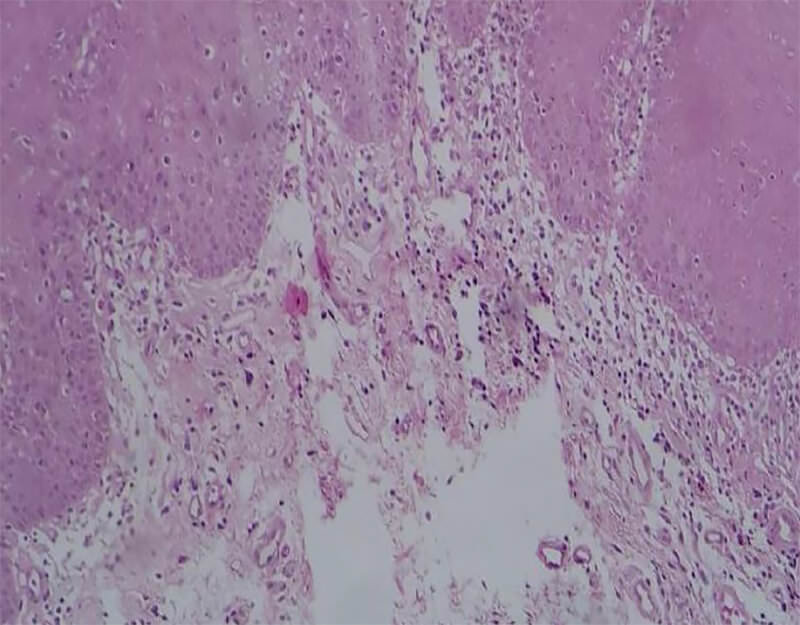

Interesantemente en 8 de los pacientes se observaron queratinocitos cargados de melanina a nivel de la capa basal, de los cuales 3 pacientes correspondían al grupo de individuos con diagnóstico de LECC, 5 correspondientes al grupo de LES (figura 3).

Figura 3. Presencia de melanina en queratinocitos basales, la cual se extiende hasta el corion. Se aprecian abundantes melanófagos. Microfotografía coloración H&E a 40X.